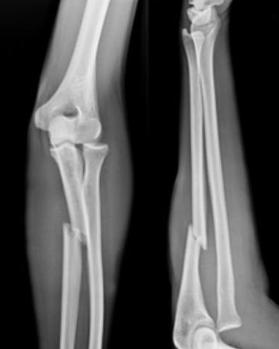

♥桡骨远端骨骺分离

在人体骨骺损伤中,桡骨远端为最易发生之部位,几乎占全身骨骺损伤的半数,即40%~50%。